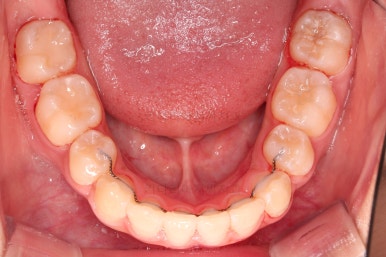

치료 종료시의 모습이에요.

총 21개월 걸렸고요.

동래교정치과의 전후 사진을 비교해 볼게요.

치여링 가지런해졌고, 교합과 중앙선 등 입안의 모습이 매우 좋아졌어요.

불규칙하게 마모되어 있던 치아의 개별 형태도 약간씩 다듬어 드렸고요.